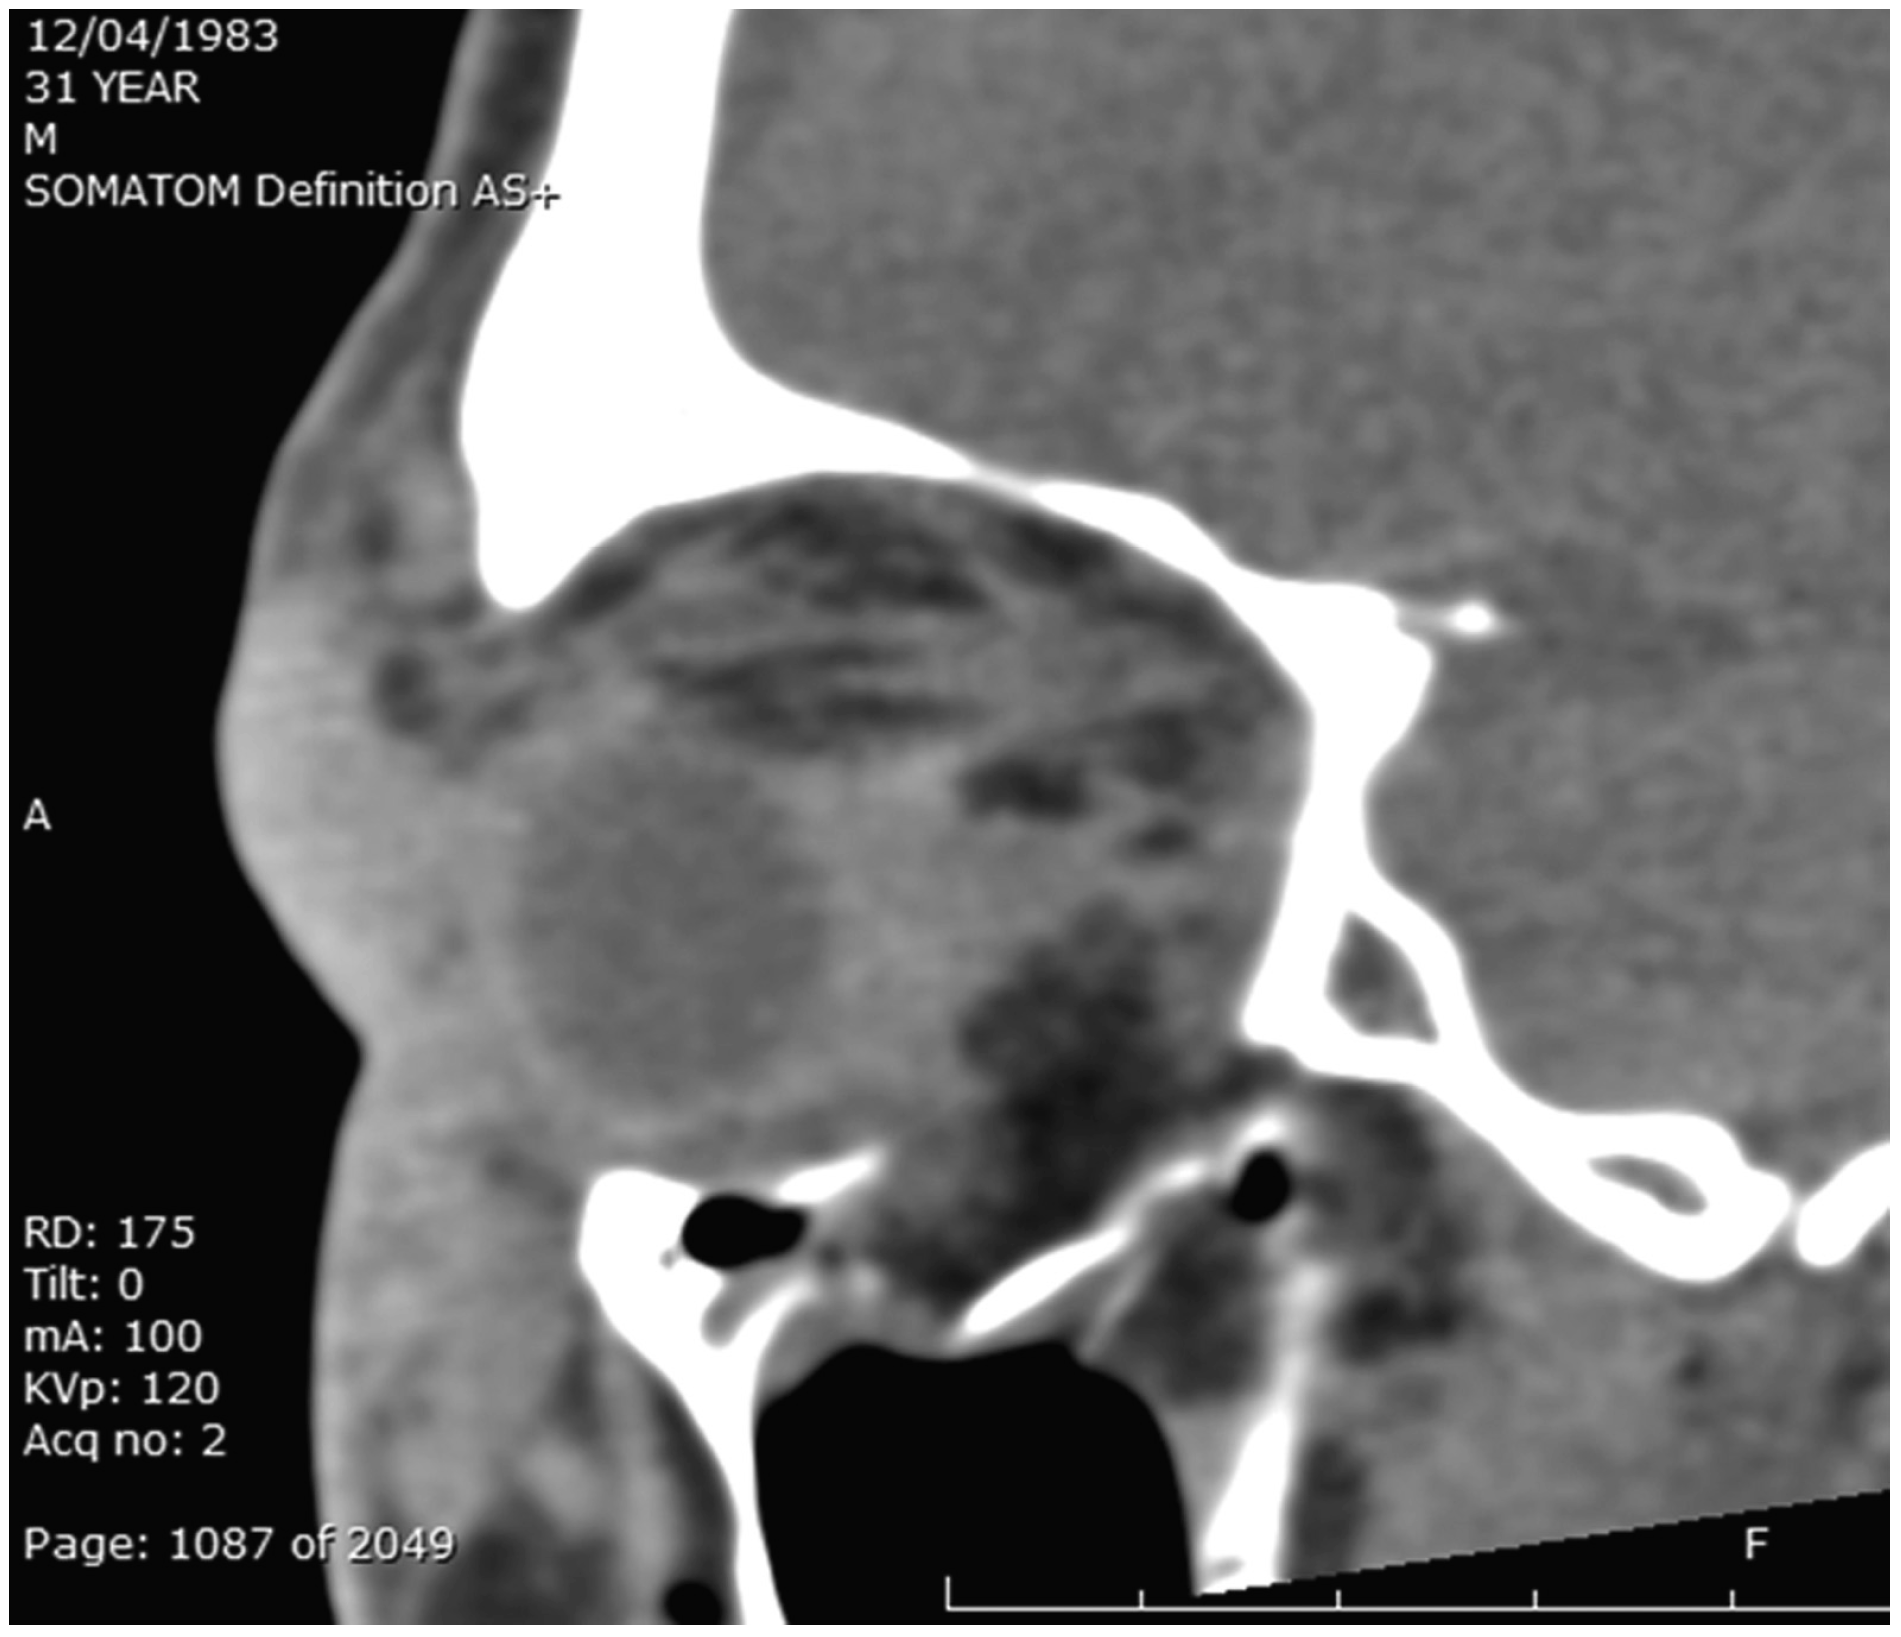

The postprocedure intraocular pressure was 23 to 29 mm Hg and there was a palpable reduction in orbital tension. Subsequent orbital imaging (Figure 1, Figure 2 and Figure 3) confirmed a displaced/punched-out fracture of the orbital floor (unhinged, type III) [1] with fracture of the medial wall, hematoma in the orbital compartment. The globe was entrapped between the orbital rim inferiorly, hematoma posterosuperiorly, and edematous preseptal tissue anteriorly. There was no orbital foreign body.

Figure 2. Sagittal soft-tissue window CT image showing punched-out floor fracture of the orbital floor. Globe resting on the anterior orbital rim and floor. Periocular soft-tissue edema.